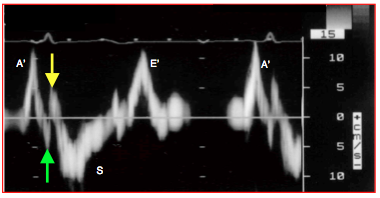

Le premier pas de l’évaluation fonctionnelle est un examen global du cœur en 4-cavités (vue mi-œsophage 0-20°), car celle-ci fournit le cadre général dans lequel vont s’inscrire les différents indices mesurés. Il permet de relever la taille respective des chambres cardiaques, leurs relations, leur dilatation et leur éventuelle hypertrophie. Cette vue générale est capitale pour intégrer les calculs détaillés qui n'expriment qu'une vue partielle de la réalité. Tout résultat ultérieur doit être compatible avec la silhouette fonctionnelle des cavités et des gros vaisseaux. L'image 4-cavités permet aussi quelques observations intéressantes (Figure 25.170).

Figure 25.170 : Vues 4-cavités 0° pour l'évaluation visuelle de la fonction du VG. A: cœur normal; la paroi du VG est musclée, la taille du VG et de l'OG est normale, la zone apicale apparaît pointue, la fraction d'éjection est 0.7. B: insuffisance chronique du VG; le ventricule est dilaté, sa paroi amincie, la zone apicale est arrondie, le débattement du feuillet antérieur de la mitrale est faible (flèche verte). C: lorsque la fonction du VG est normale, le débattement du feuillet mitral antérieur est ample; le feuillet est presque parallèle au septum en diastole. D: insuffisance mitrale restrictive sur dysfonction et dilatation du VG; les feuillets sont retenus en-dessous du plan de l'anneau mitral en systole (trait pointillé blanc) et la valve fuit.